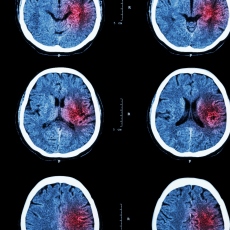

A stroke is a medical emergency. There are two types - ischemic and hemorrhagic. Ischemic stroke is the more common type. It is usually caused by a blood clot that blocks or plugs a blood vessel in the brain. This keeps blood from flowing to the brain. Within minutes, brain cells begin to die. Another cause is stenosis, or narrowing of the artery. This can happen because of atherosclerosis, a disease in which plaque builds up inside your arteries. Transient ischemic attacks (TIAs) occur when the blood supply to the brain is interrupted briefly. Having a TIA can mean you are at risk for having a more serious stroke.

It is important to treat strokes as quickly as possible. Blood thinners may be used to stop a stroke while it is happening by quickly dissolving the blood clot. Post-stroke rehabilitation can help people overcome disabilities caused by stroke damage.